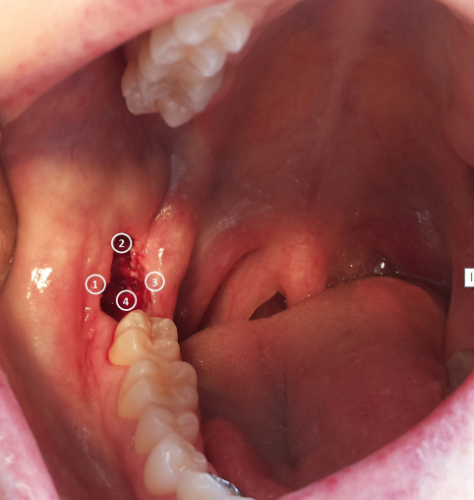

Hình 5.2: Vị trí chiếu LLLT trong miệng: (1) phía ngoài, (2) phía xa, (3) phía trong, (4) phía gần huyệt ổ răng.